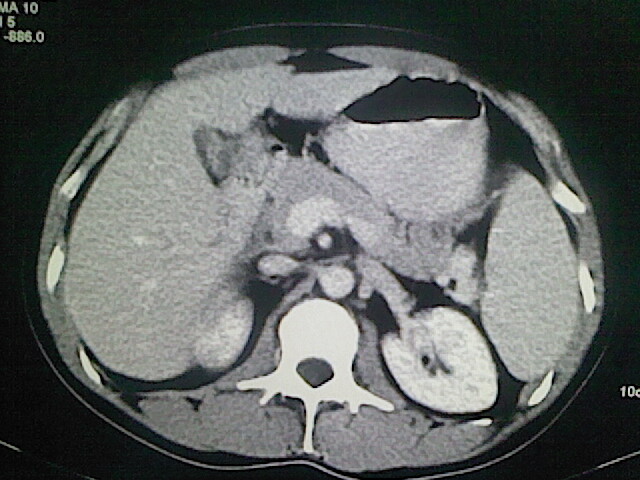

以下是引用卜一在2009-3-14 9:49:00的发言:[br]胆囊萎缩,胆囊壁不规则增厚,内部结构模糊,增强明显强化。另:肝左叶外侧段肝囊肿。支持:慢性胆囊炎!高度可疑:胆囊癌!

以下是引用余辉在2009-3-14 8:48:00的发言:[br]1)慢性胆囊炎。2)肝左叶外侧段肝囊肿。3)脂肪肝。[br]支持,胆囊萎缩,密度增高,不知b超具体有何提示,钙胆汁?结石?

以下是引用jiangjing在2009-3-14 10:18:00的发言:[br]1)慢性胆囊炎。2)肝左叶外侧段肝囊肿。3)脂肪肝。4.】建议行肝功能检查